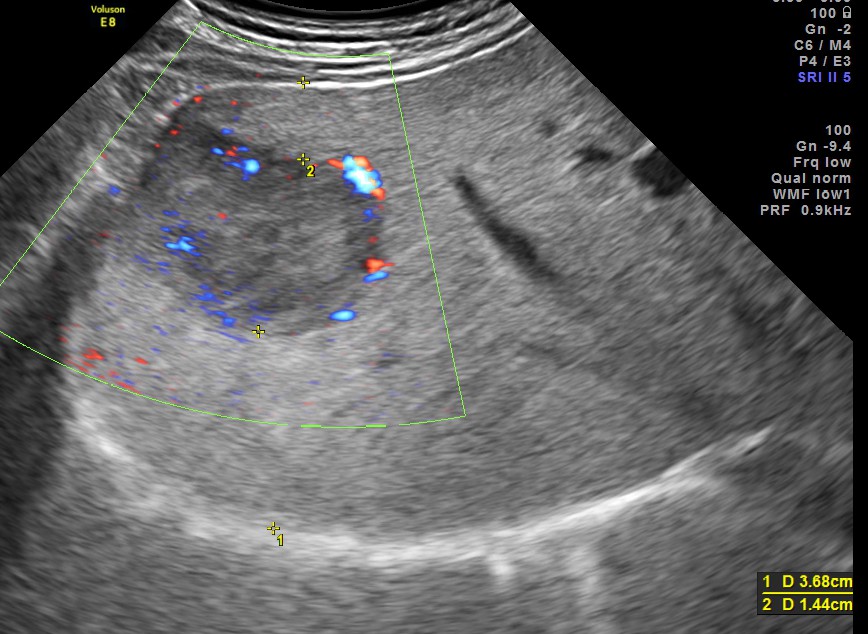

3 d reconstruction shows the solid nature and vascularity around and within the nodule.

The appearance of this nodule was suggestive of a metastatic nodule with the increased vascularity around and within.